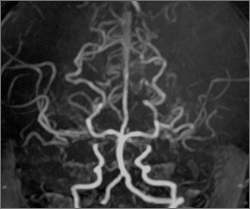

4歳女児症例 脳MRA検査

治療前